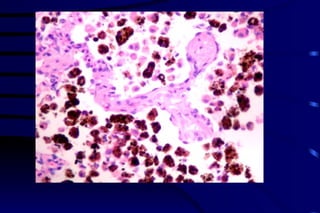

Liquefactive necrosis Bacterial or fungal infections Central nervous system Amebiasis

Liver abscess: Liquifactive necrosis